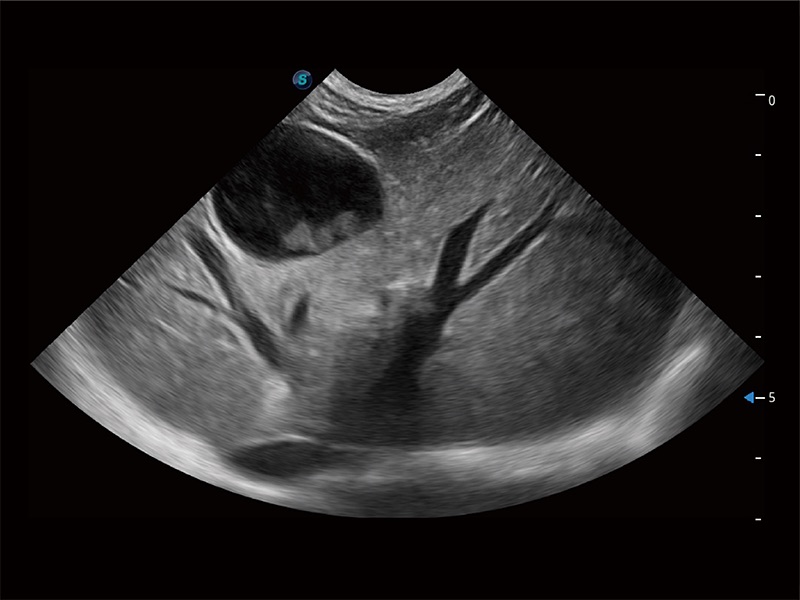

(犬)肠道

(犬)肝脏